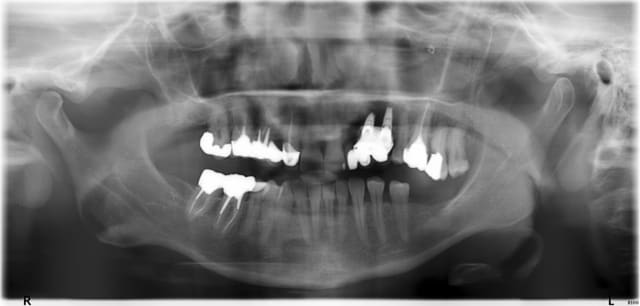

Les implants ou plutôt l'os autour semblent corrects sur la retroalveolaire donc pas le feu au lac.

Les implants n'ont pas l'air trop mal positionnés mais le boulot de prothèse je comprends vmt pas le projet :D.